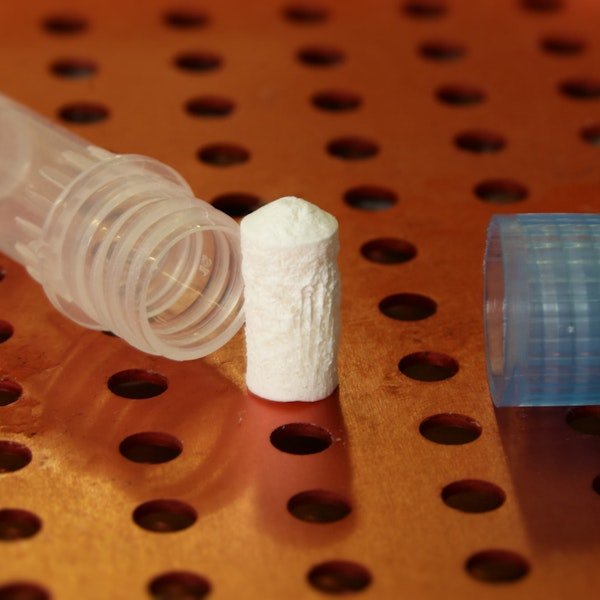

Bone Graft

Jawbones atrophy following tooth loss, which can make it difficult to receive dental implant-supported restorations. Fortunately, a bone graft can restore your jaw, improving your candidacy for other restorative treatments.